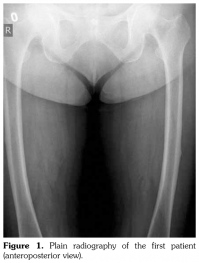

Case 1– A 73-year-old female patient presented with low back, knee, and anterior thigh pain. Pain severity was 8 over 10 point according to visual analog scale. She had difficulty in walking because of pain. She had a history of arthroscopic knee surgery for meniscal pathology in her left knee five years ago. She had chronic low back pain due to L4-5 disc herniation and lumbar spinal stenosis. She had been treated for osteoporosis with alendronate for two years, then with salmon calcitonin for two years and ibandronic acid for a year. Neurological examination was normal. Plain radiographs revealed bilateral lateral cortical thickening in the femur (Figure 1). Magnetic resonance imaging was done to rule out fracture. Bone scintigraphy showed increased uptake in bilateral femoral diaphysis. Routine biochemical tests were normal except increased urinary deoxypyridinoline. Urinary deoxypyridinoline level was 63 nM/mMCre (normal range: 3-7.4 nM/mMCre).

Bone scintigraphy of the patients revealed increased uptake in femoral diaphysis. Atypical bisphosphonate associated subtrochanteric and femoral shaft stress fractures show specific appearance on bone scintigraphy characterized by mild uptake in multifocal endosteal thickening of the lateral femoral diaphysis.(11)